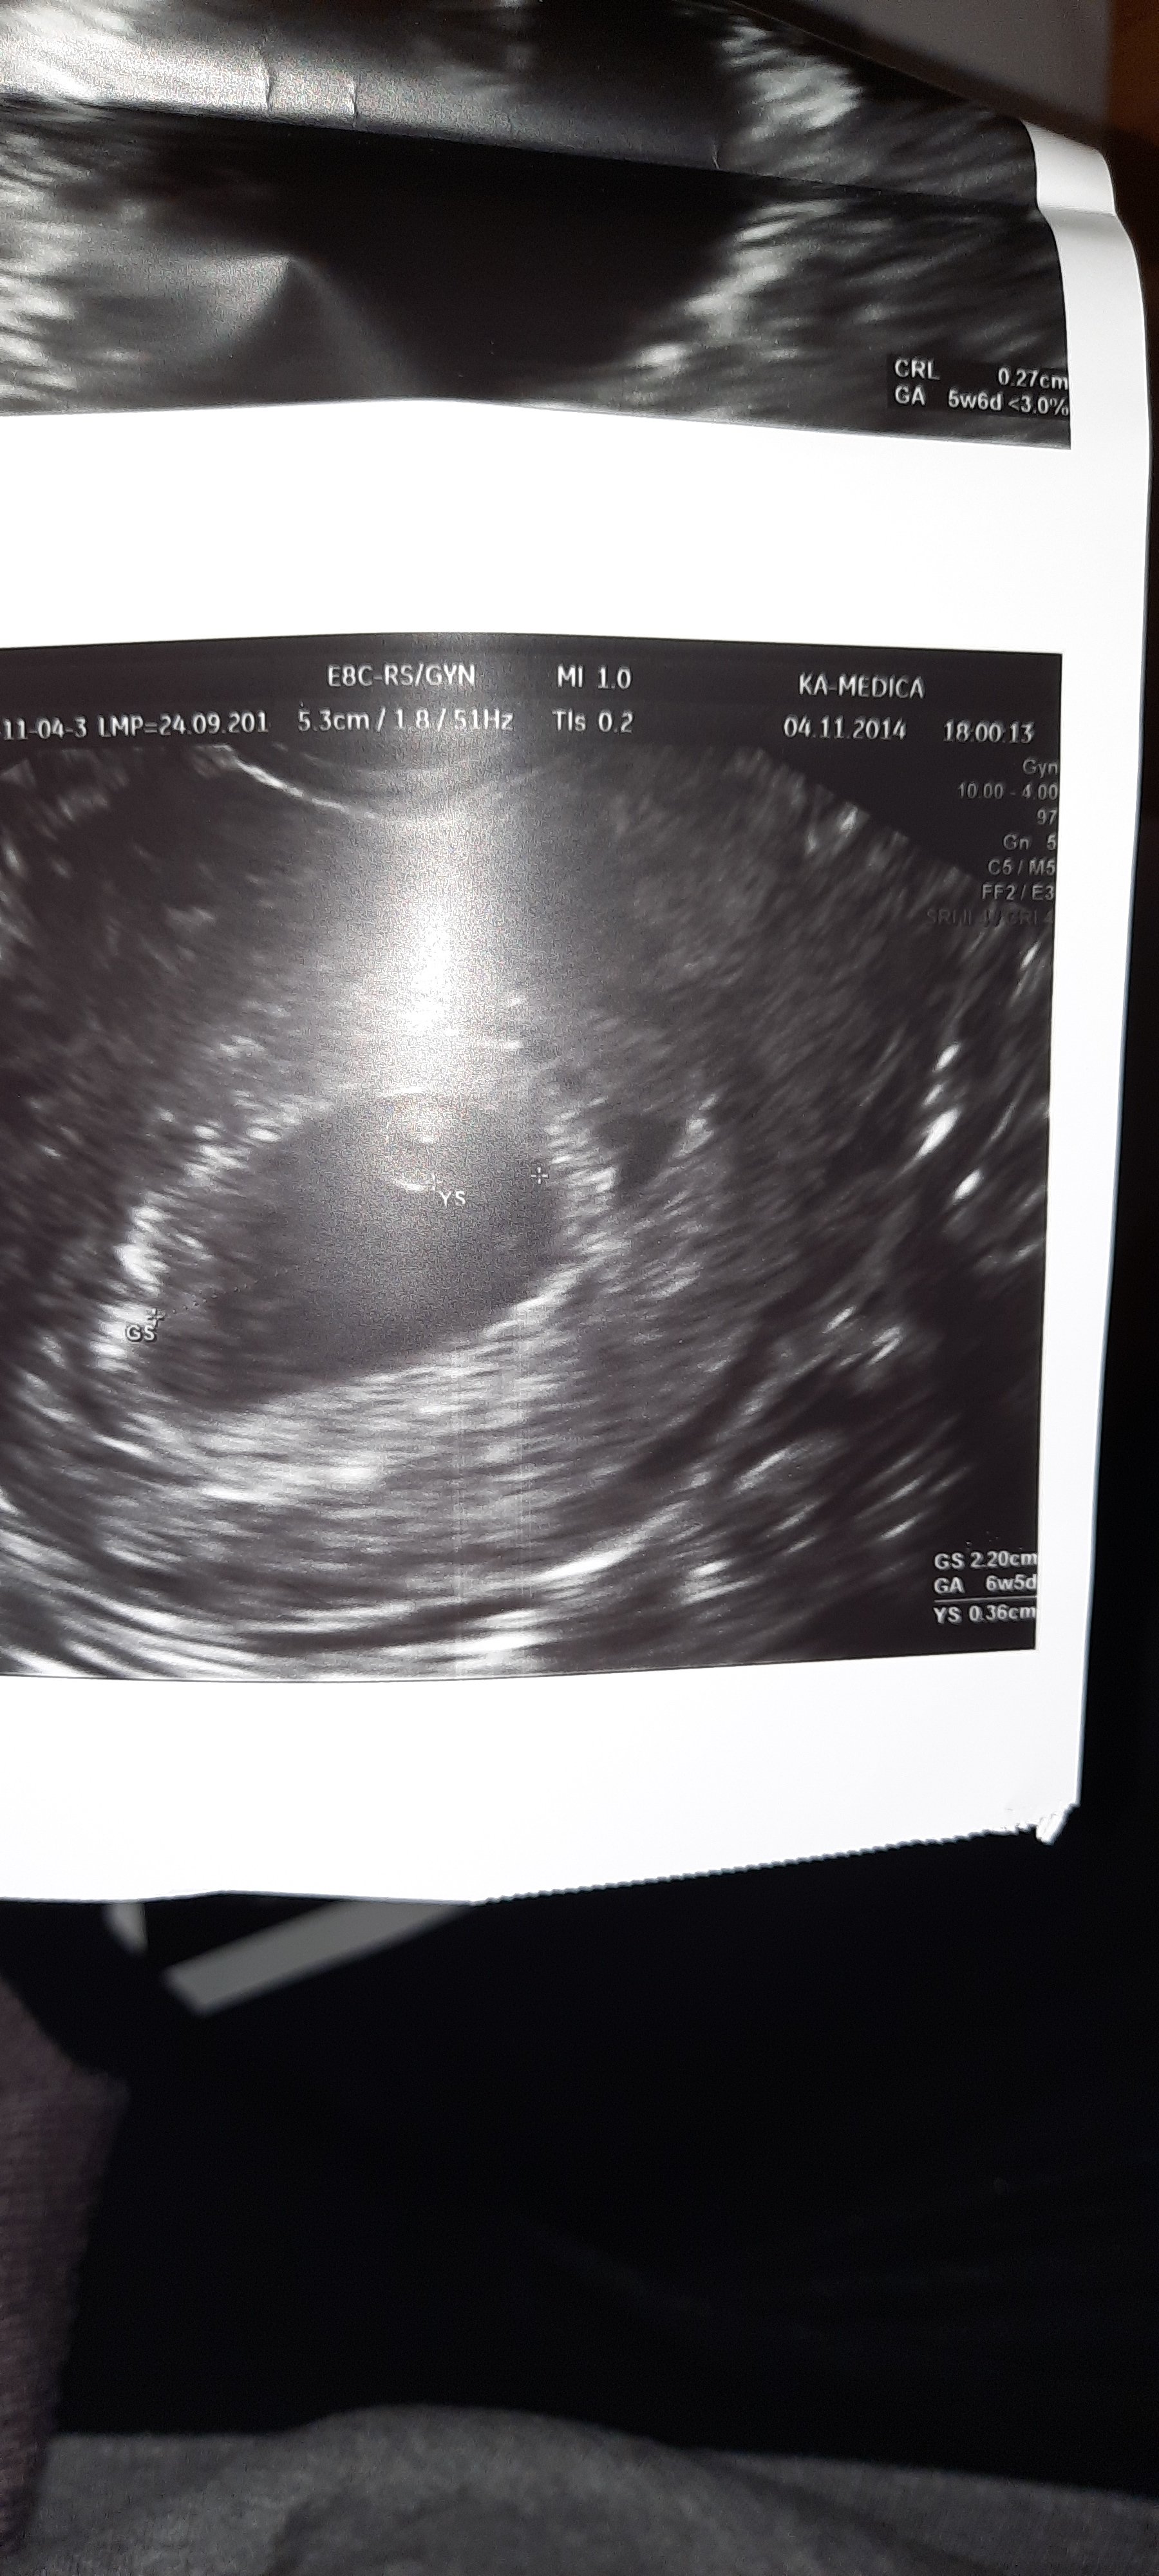

Ja nie mam wymiarow na drugiej ale mam z obu ciaz z 6tyg

Załączniki

• 20201116_164243.jpg

20201116_164243.jpg

1 MB · Wyświetleń: 199

• 20201116_164431.jpg

20201116_164431.jpg

895 KB · Wyświetleń: 201